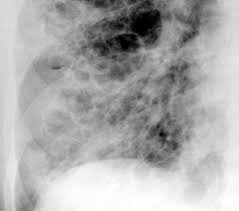

Comprometimento Pulmonar Na Esclerose Sistemica Revisao De Casos

Comprometimento Pulmonar Na Esclerose Sistemica Revisao De Casos from www.scielo.br